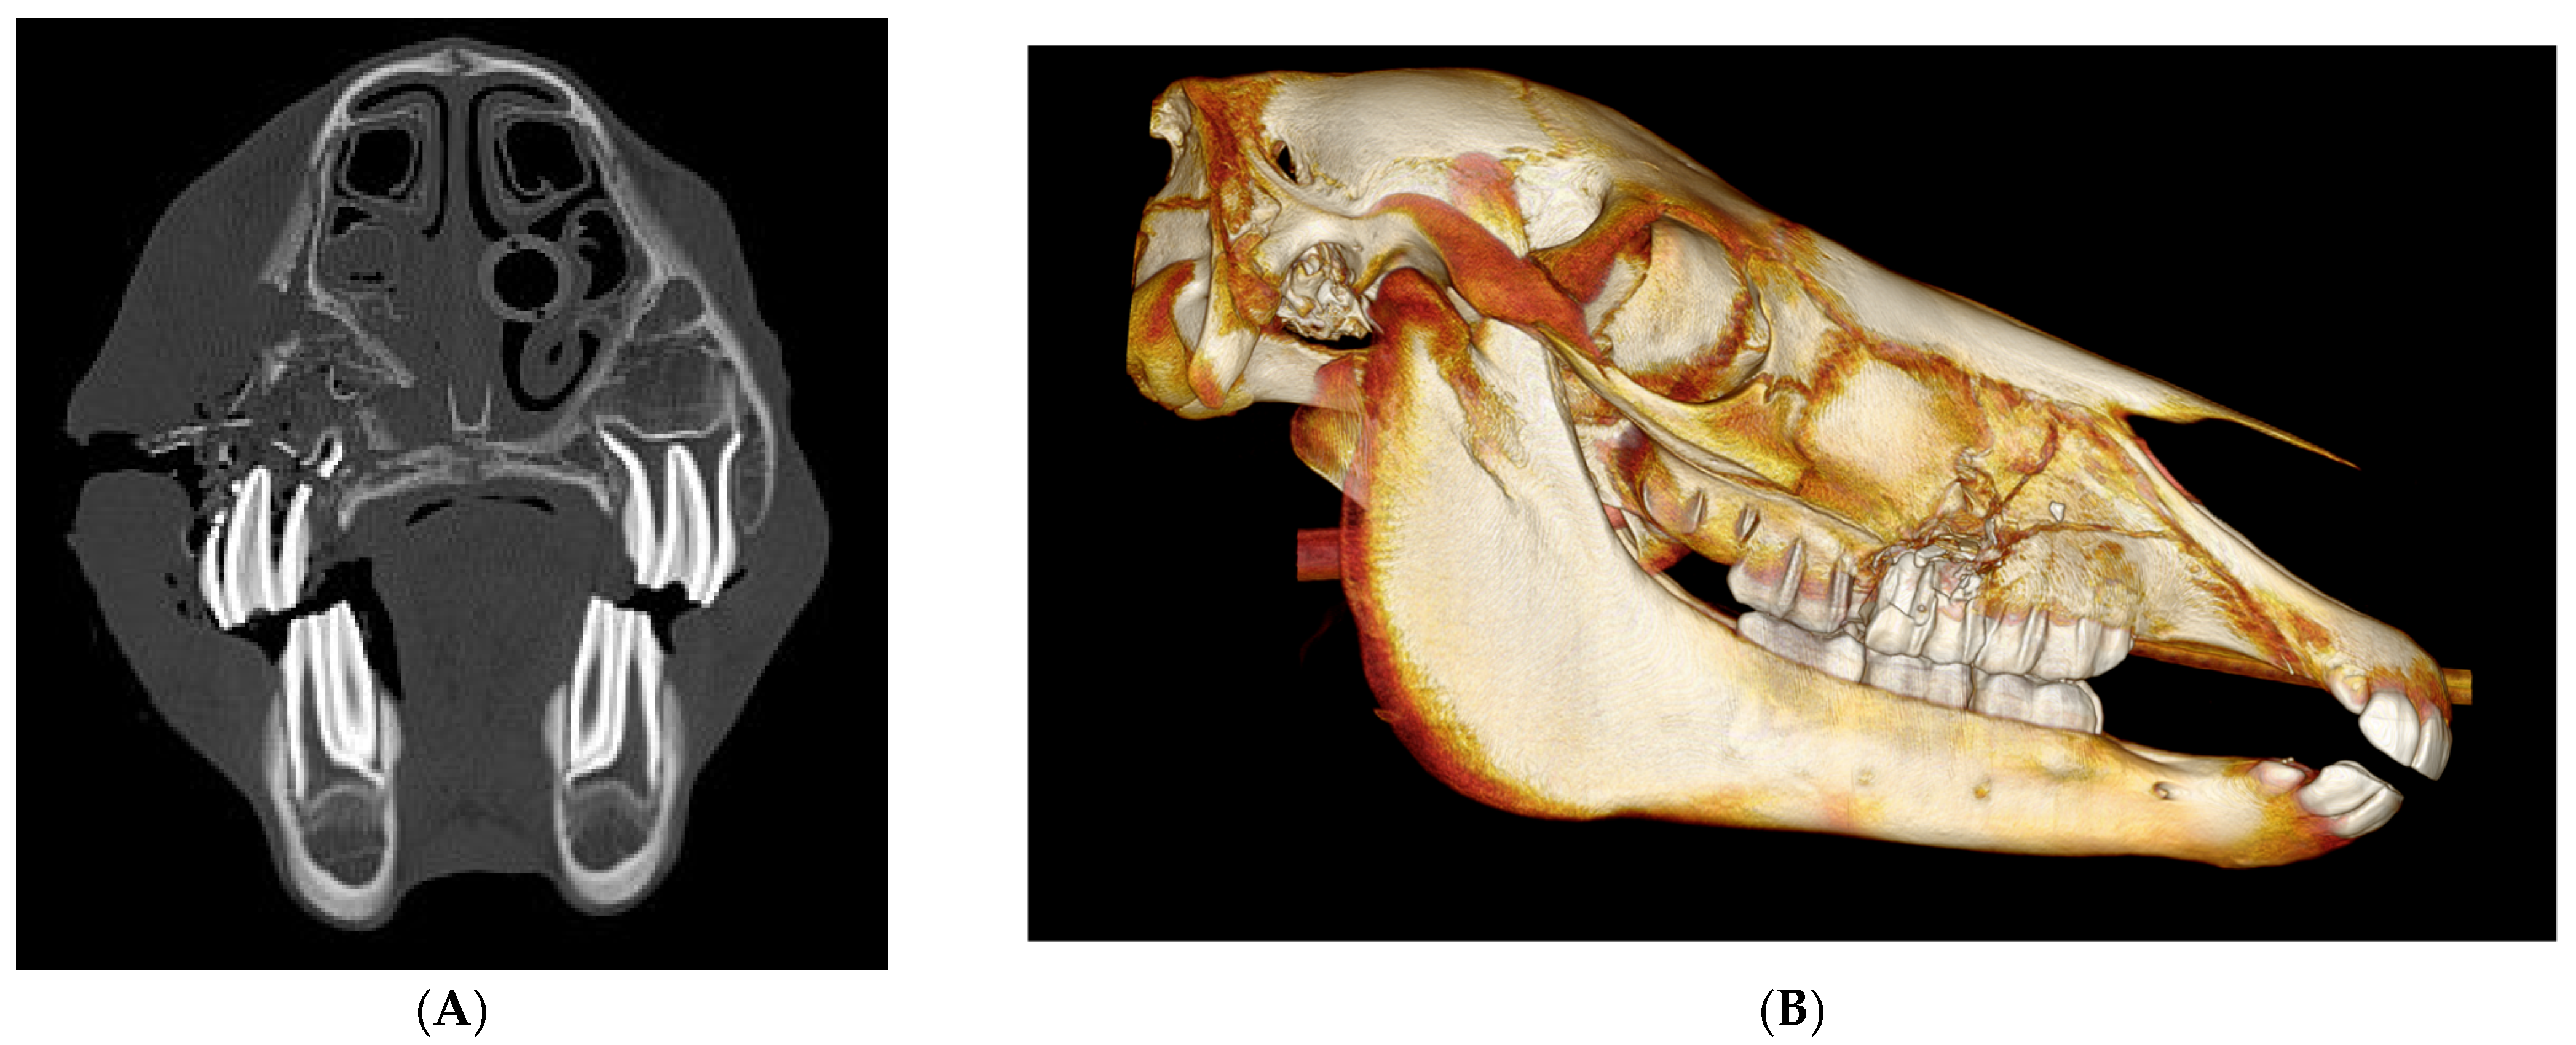

| 1 | 5 yo, G, WB | Unilateral Closed | Maxillary | Conservative | No | No | Good | |

| 2 | 18 yo, G, Unknown | Unilateral Closed | Maxillary | Maxillary Sinus Ventral conchal sinus Nasolacrimal duct | Conservative | No | No | Good |

| 3 | 12 yo, G, WB | Unilateral Open | Maxillary | Caudal maxillary sinus Nasolacrimal duct Root fracture 210 | Sinoscopy Bone fragment removal | No | No | Good |

| 4 | 9 yo, G, WB | Unilateral Open | Frontal Lacrimal Maxillary Nasal | Conchofrontal sinus Orbit Retrobulbar fragments | Sinoscopy | Yes | Sequestrum | Good |

| 5 | 12 yo, M, Polo Pony | Bilateral Closed | Nasal Frontal | Maxillary, conchofrontal, ventral conchal sinus Orbit Nasal septum collapse | Conservative | Yes | Narrowing left conchofrontal sinus Cosmetic | Fair to Good |

| 6 | 17 yo, M, Welsh | Bilateral Closed | Frontal Nasal Lacrimal | Caudal maxillary, dorsal conchal sinus Suture periostitis | Conservative | Yes | Suture periostitis Cosmetic | Fair to Good |

| 7 | 14 yo, M, TB | Unilateral Open | Nasal | Sinusitis dorsal conchal sinuses | Bone fragment removal Sinus Flush | No | Wound dehiscence | Good to Excellent |

| 8 | 2 months, filly, WB | Unilateral Open | Maxillary | Fracture tooth 507 | Fragment removal PMMA packing | Yes | Granuloma socket 507 | Excellent |

| 9 | 12 yo, G, WB | Unilateral Open | Maxillary Zygomatic | Maxillary and ventral conchal sinusitis fracture 210 Infraorbital canal | Sinoscopy fragment removal | Yes | No | Good |

| 10 | 5 yo, M, WB | Unilateral Closed | Maxillary Nasal Frontal Lacrimal | Orbit Rostral maxillary/ventral conchal sinusitis | Conservative | No | No | Excellent |

| 11 | 7 yo, G, WB | Bilateral Closed | Nasal | Suture periostitis Nasolacrimal duct | Conservative | No | No | Good |

| 12 | 7 yo, S, Lusitano | Unilateral Open | Nasal Maxillary Incisive | Rostral maxillary and ventral conchal sinusitis | Conservative | Yes | No Cosmetic | Good |

| 13 | 15 yo, G, WB | Unilateral Closed | Maxillary Nasal | Periapical infection 106, 107 and 108 | Oral extraction 106, 107 and 108 | No | Orocutaneous fistula | Fair |